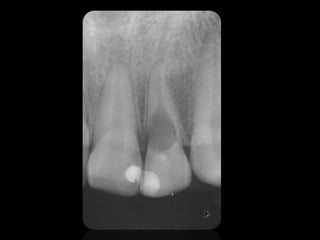

QUISTES